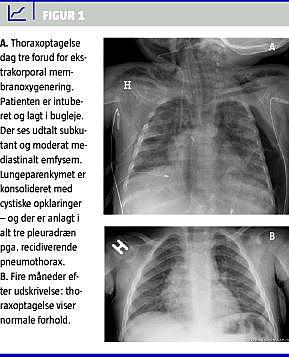

Sygehistorie